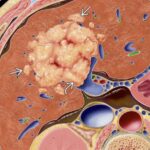

Ung Thư Tế Bào Gan (HCC) | Bài giảng CĐHA *

HCC (Hepatocellular carcinoma) là u ác tính nguyên phát thường gặp nhất và thường xảy ra trong bệnh cảnh xơ gan. HCC là do phát sinh từ nốt loạn sản tiền ác tính, biệt hóa ngược dần từ độ ác thấp đến độ ác cao trên mô học. HCC đơn ổ ở 50%, đa ổ 40% và lan tỏa 10%. Alpha-fetoprotein cao trong 50-70% bệnh nhân. Có ba dạng phát triển của HCC gồm khối đơn độc (50- 60%), đa ổ và thâm nhiễm lan tỏa. Xâm lấn tĩnh mạch cửa gặp ở 1/3 số bệnh nhân, và thường gặp nhiều hơn ở dạng thâm nhiễm lan tỏa…